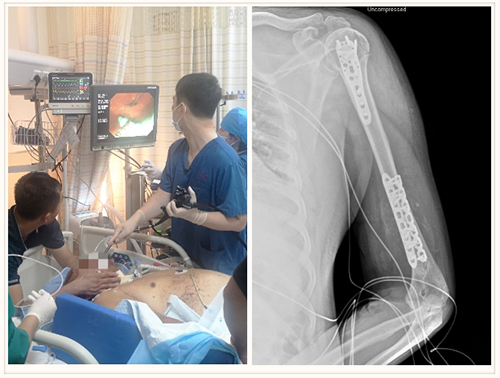

东院创伤四科(创伤重症病房)立即启动院内救治流程,与东院创伤一科、血管外科、消化内科联合组成MDT团队,经过共同讨论分析,制定诊疗计划。由消化内科床旁放置肠梗阻导管行全小肠减压,辅以灌肠、肠动力药物、中药等,尽快缓解肠梗阻,以免发生肠缺血、坏死、腹腔高压综合征等危及生命;病情平稳后,创伤一科行手术治疗,采取创伤控制理念,在不造成机体重大创伤、应激的同时尽早使骨折稳定。针对下肢血栓及肺动脉栓塞,考虑非急性期,暂不溶栓,在严密观察下行抗凝治疗,警惕病情进一步加重的风险。东院创伤四科(创伤重症病房)进行综合管理,重点解决患者的营养不良、腹腔感染、肺部感染、呼吸道管理、意识不清等情况。MDT团队定期召开会议,动态调整诊疗方案。

经积极救治,患者肠梗阻导管逐渐运行至回盲部,全小肠减压的目标得以实现,左侧肱骨多发骨折得以固定,患者疼痛、躁动等明显减轻,翻身、护理等变得更加容易。